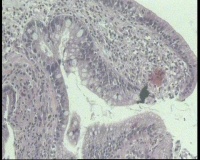

请老师看看胃角溃疡,上皮有轻度非典型增生吗?

性别年龄58岁临床诊断胃角溃疡

一般病史胃角:近后壁见一处圆形溃疡,大小0.6x0.6厘米,底附黄白苔,周围粘膜充血水肿

标本名称胃镜活检

大体所见胃镜活检组织

镜下胃粘膜腺体肠化,局灶腺上皮细胞核大

有坏组织,符合溃疡,腺体肠化,轻度不典型增生。

溃疡+萎缩+肠化+修复。

有肠化和修复性增生。